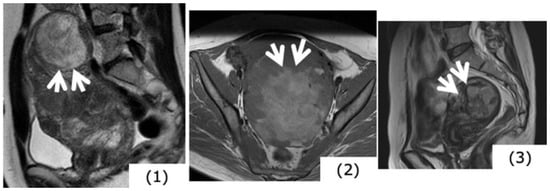

Figure 5.

Magnetic resonance images of leiomyosarcoma (age, 49 years). (A,B): T2-weighted images sagittal sections, (C): T1-weighted axial section, (D): contrast T1 fat-suppression axial section. In the myometrium, heterogeneous high signals are presented with T2-weighted images, and with T1-weighted images, there is confirmation of mass showing faint high signals considered to be hemorrhage. In the contrast T1 fat-suppression image (D), a poorly contrasted area considered to be necrosis is found, while in (B), the fundus uteri side shows extremely thin myometrium, together with finding a portion considered to be extraserosal exposure, with ill-defined tumor borders (arrow).